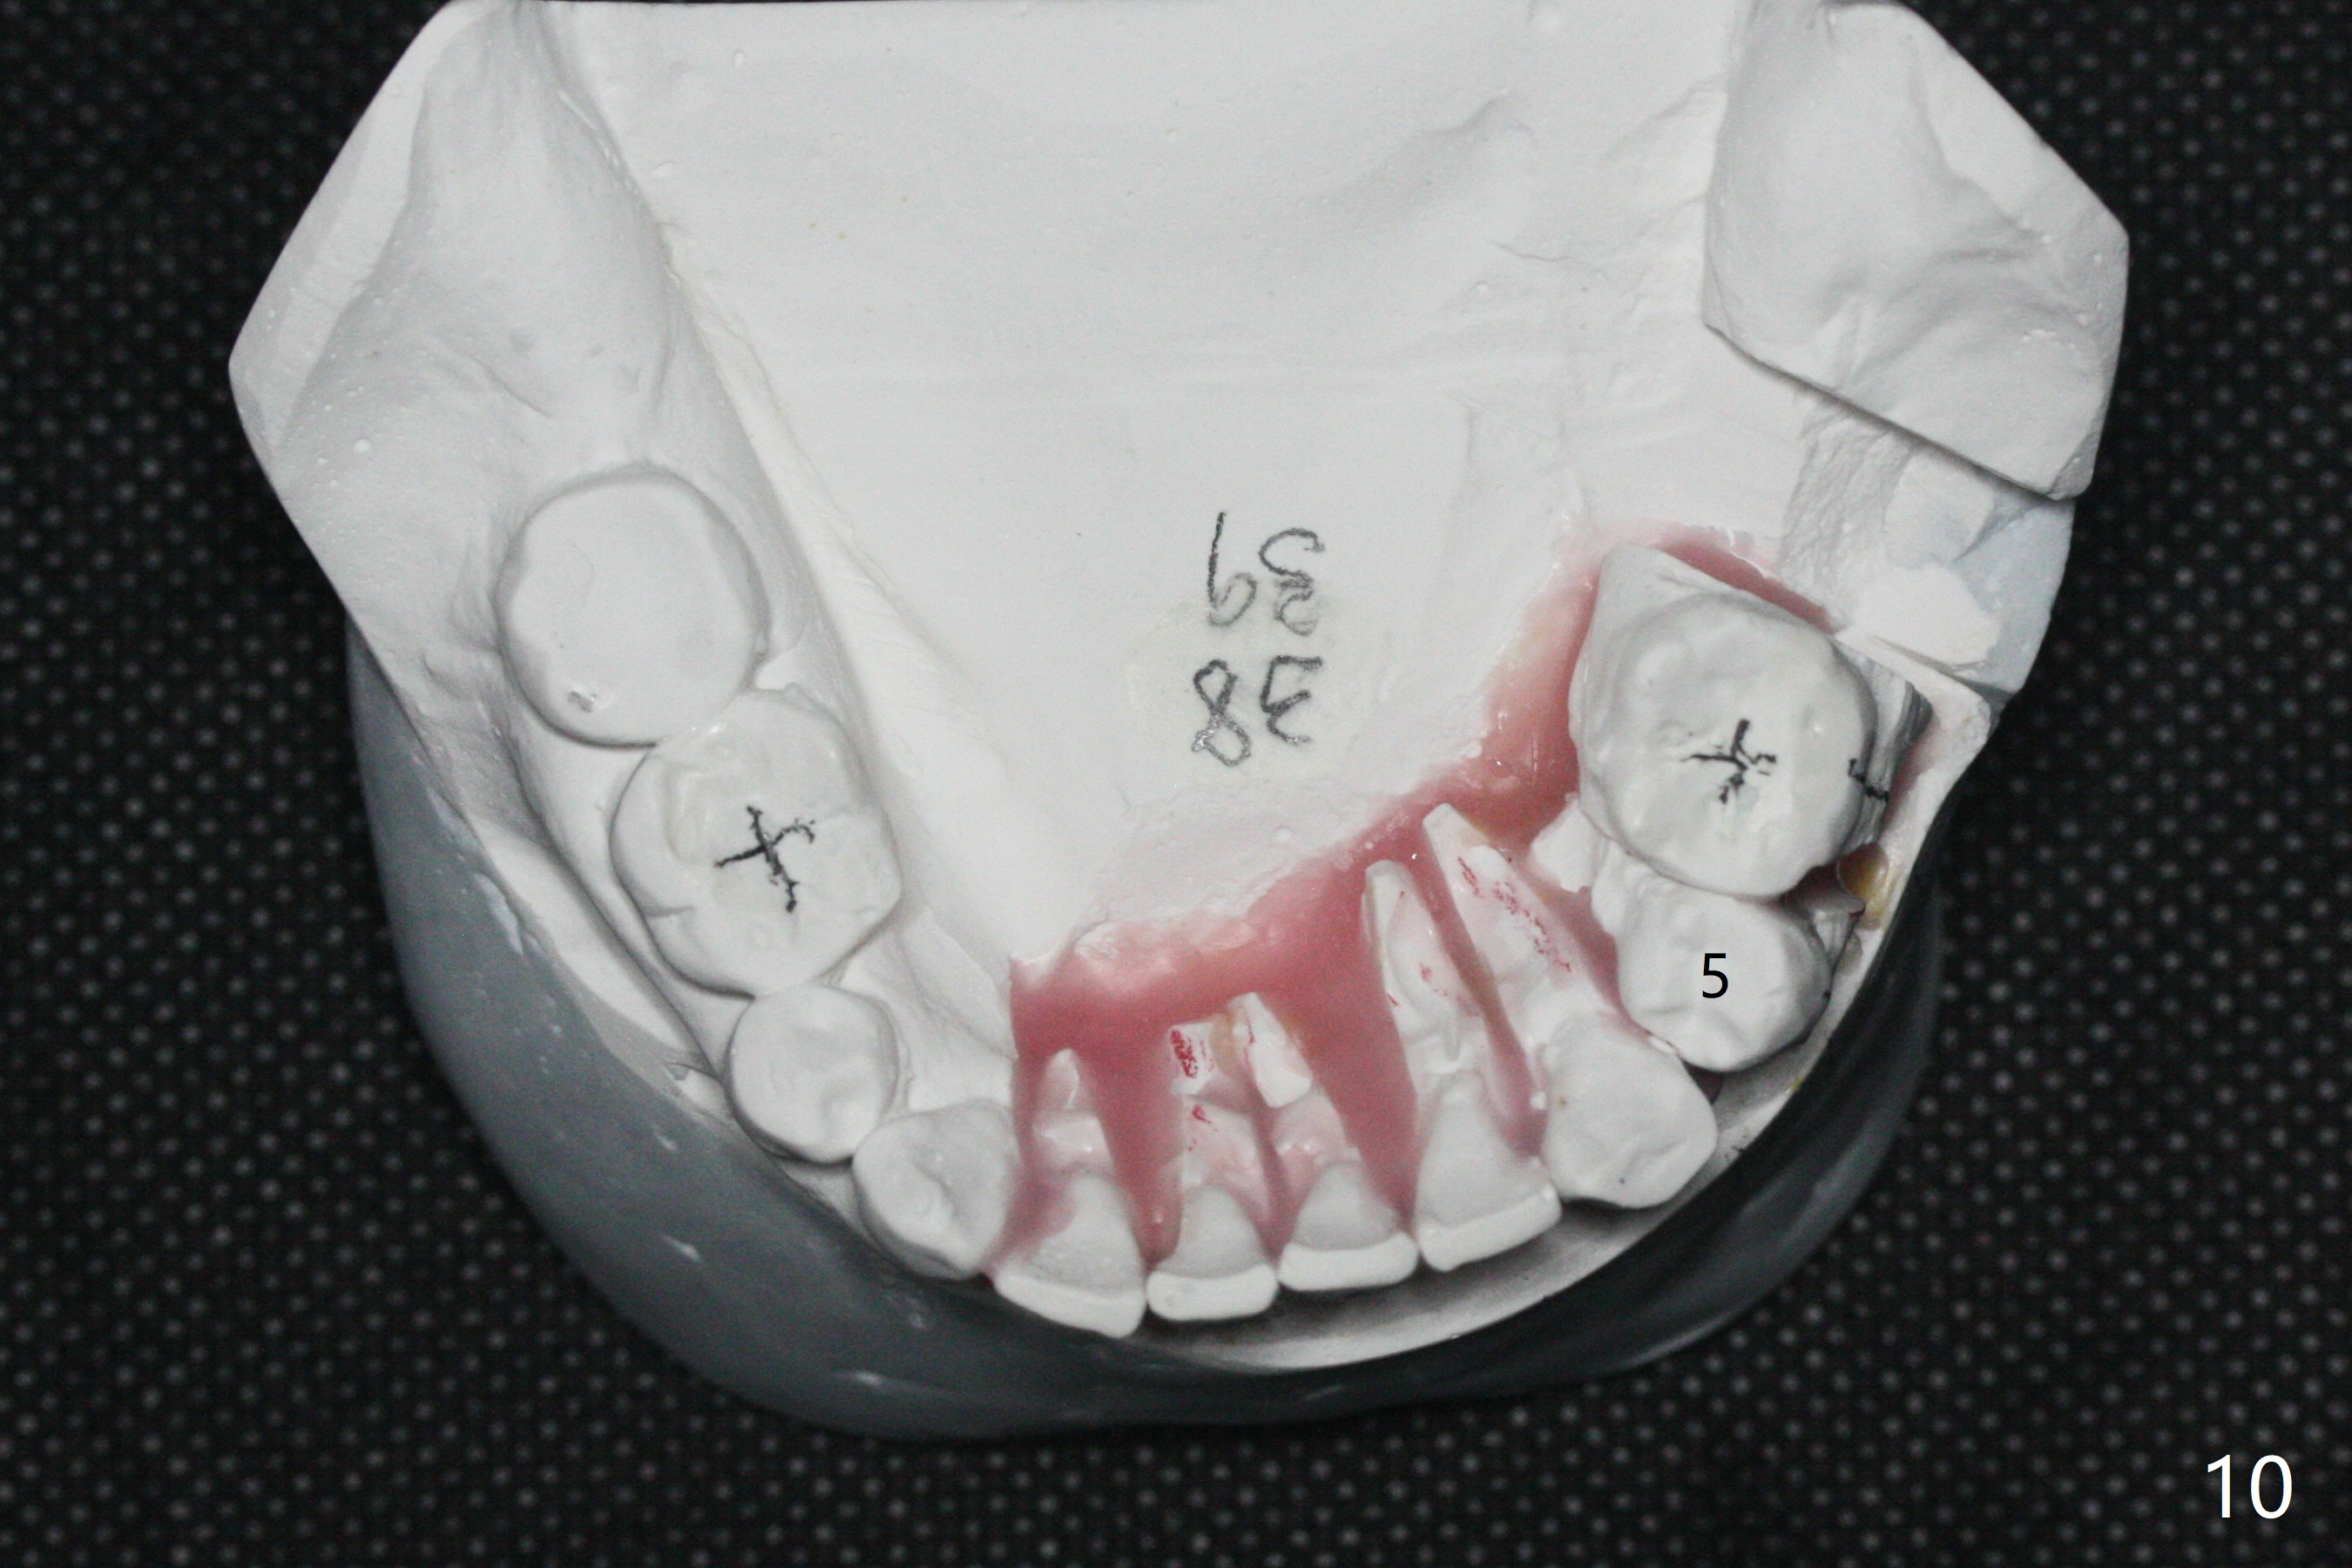

A 54-year-old man remains difficult in mastication in spite of implant placement at #14 and 31 (Fig. A, B, E, including screw loosening (poor trajectory at #14)). In addition to 2 more implants at #15 and 18 with guide, malocclusion seems to be necessary to be addressed (Fig.1-5). It appears that UR, LL4 should be extracted for orthodontic treatment (Fig.6-10). To reduce screw loosening, IS guide will be used to place IBS (5x9mm) and tissue-level (5x11mm) implants at #15 (PRF)and 18, respectively. If the one at #14 or 15 keeps loosening, splint #14 and 15 crowns. In fact the patient agrees with limited ortho (UR7 cross bite).